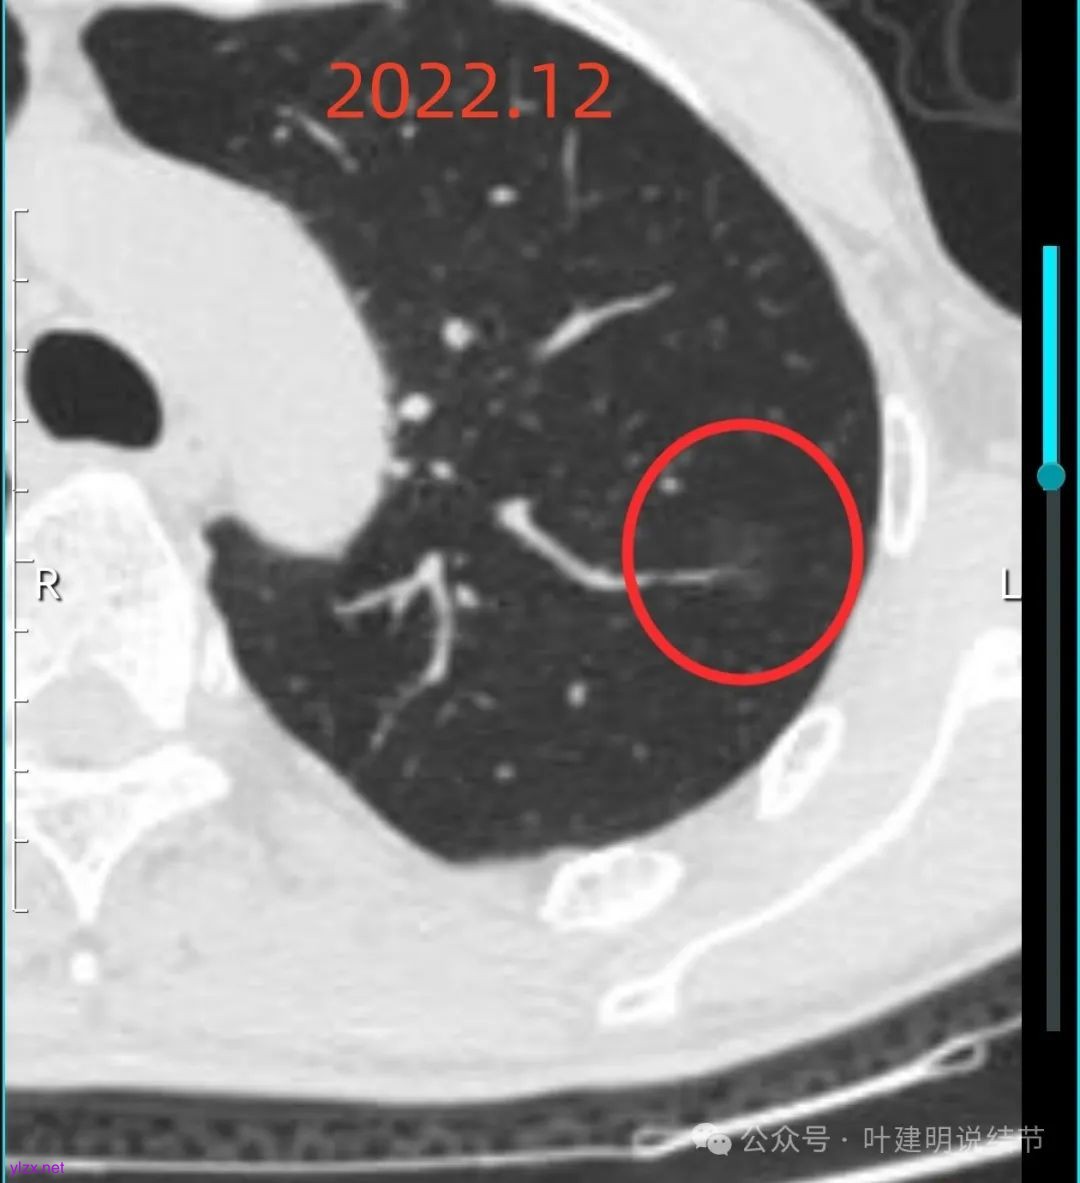

左上这个病灶是淡磨玻璃密度,虽然较淡但轮廓与边界却较为清楚,也有血管进入,倒是要考虑恶性范畴的,但这种密度仍是原位癌可能性较大。

病灶内没有明显实性成分,整体轮廓较清。

左上病灶血管进入了病灶且有异常增粗,边缘有淡的细毛刺的样子。

灶内血管明显,管壁略毛糙,有异常增粗,红色箭头处有点状高密度,边缘有毛刺征。